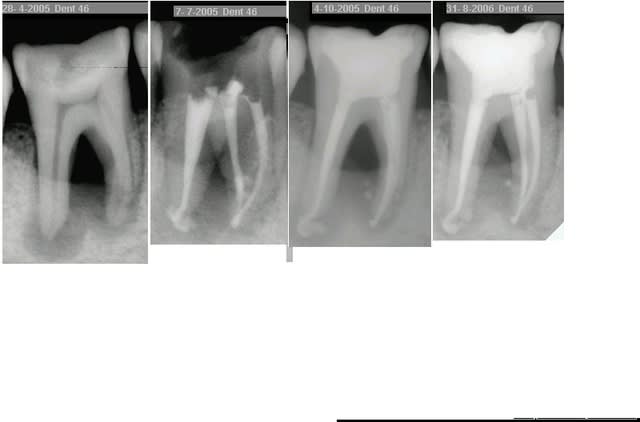

alors là.... rep endo pas simple mais sans soucis... sf que entre la radio pre et post reprise, il y a comme qui dirait un passage de pate par une perfo du plancher....mais j'ai pas vu de perf du plancher....

bref...vous pensez que c' est quoi? une perf obturée? un ttt endo du desmodonte? ...

moi qui n'ai jamais osé lancer le debat du petit dépassement de pâte en cas de lésion apicale (peut être déjà traité d'ailleurs?), je suis totalement rassurée...pour ce qui est du desmodonte, ça ressemble quand même bien à une perfo, le plancher avait l'air très fin sur la radio préop..?

une remontée de pate peut etre....attends une radio a distance et tu verras la pate se dissocier et t'eclairer un peu...

si tu es sûre qu'il n'y a pas de perfo, ne serait-ce pas une "remontée" de pâte par l'apex? C'est certes volumineux mais on ne sait jamais

Je crois pas trop a la perf, tu aurais pas un tracé comme ça. De toute façon c'est RX a 3 semaines puis à 1 mois puis a 3 mois et soit les peches se barrent soit, de toute façon..

ce qui m'interpelle,n'est finalt pas la cause mais les conéquences

si pareille remontée de pâte cela signifie que au niveau osseux l'espace interadiculaire est lésé,non?

Il peut y avoir de tres petites communications au niveau du plancher. Alors pourquoi pas un de ces "canaux" qui donnent passage a la pate lors de l'obturation.

En effet, d'accord avec ce qui a été dit : si tu avais eu une perf du plancher, la pâte serait resté très localisée sous celui-ci. Là, la pâte a sans doute suivi un trajet de fistulisation.

Comme Athos ou Gai-luron, ça me fait aussi penser à une remontée de pâte dans une voie de fistulisation.

j' ai fait cette endo en fin juin 06...et j' avais oublié cette image que je voulais vous poster...

bref...depuis, Mme X est revenu, elle avait eu un peu mal après la reprise d'endo faite sans anesth locale, et voici la rx du jour....

Comme quoi, du moment que c'est "propre", un dépassement n'empêche pas la cicatrisation...

Au fait... je vote OUI au référendum pour le dépassement "raisonné" ds les reprises d' endo.....

Et au fait aussi, je ne suis pas sure que sans laser, j' eu aussi une bonne decontamination canalaire et une cicat aussi rapide....z'en pensez quoi????